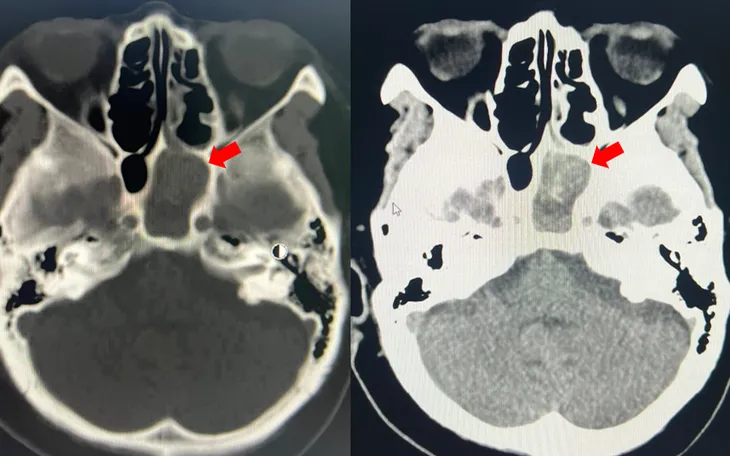

BSCKI. Nhâm Tấn Đạt cho biết, kết quả chụp CT scan và các xét nghiệm cho thấy người bệnh có khối nấm trong xoang bướm trái kèm nhiễm trùng xoang. Bệnh nhân đồng thời mắc tăng huyết áp, bệnh thận mạn giai đoạn III và đái tháo đường type 2 - những yếu tố làm bệnh dễ tiến triển nặng hơn.